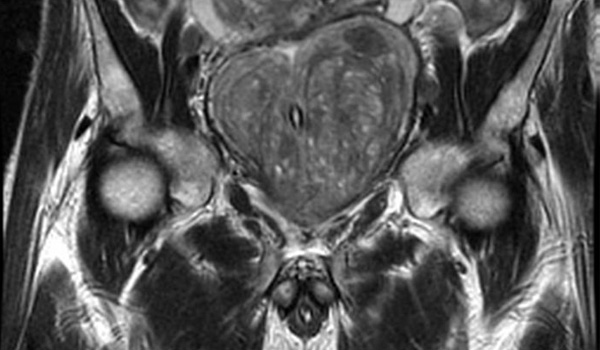

Imágenes por resonancia magnética en la detección del cáncer de próstata:  revisión sistemática y metanálisis

07 mayo 2024

Los resultados de esta revisión sistemática y metanálisis sugieren que la integración de la resonancia magnética en las vías de detección del cáncer de próstata se asocia con un número reducido de biopsias innecesarias y un sobrediagnóstico de cáncer de próstata insignificante, al tiempo que se mantiene la detección de cáncer de próstata clínicamente significativo en comparación con la detección solo con PSA. JAMA Oncol,  5 de abril de 2024